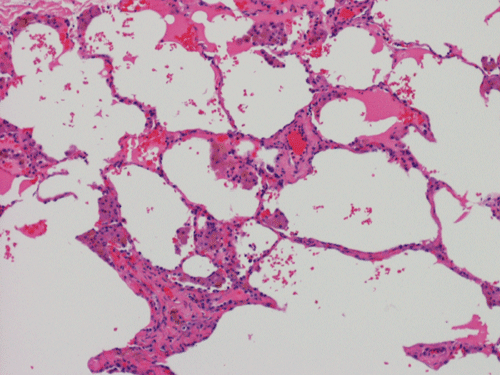

At scanning magnification (Panel A), the lung parenchyma is replaced by some coalescing fibrous nodules. The degree of involvement is variable at different fragments (Panel B and C). In the less affected areas, there are some fibrotic thickening of the septa (Panel C). In some areas, the changes are minimal and the pleural appear to be uninvolved (Panel D and E). In low to medium magnifications, these nodules of fibrosis contains a large number of hemosiderin laden macrophages (Panel F and G) admixed with fibrous tissue. The diagnostic tissue, however, is present in areas with increased cellularity. In these areas, there is a background of cells with a moderate amount of cytoplasm and bland nuclei. Some of these nuclei have kidney shape (arrow in Panel H). In some areas, many of the nuclei have a deep nuclear groove that resemble a coffee bean (arrow in Panel I). In the third type of areas, the nuclear grooving is not distinct (Panel J). Prominent eosinophilic infiltrations are almost always present. Immunohistochemistry on CD1a revealed many positive cells (Panel L). Also present in the specimen are multiple small blood vessels with thickened intima (Panel K). A Movat pentachrome stain demonstrates an internal elastic layer in these vessels and confirms that these are arteries (Panel M and N).

In up to 25%, an abnormal chest x-ray (CXR) may be the only clue to the disease in asymptomatic individuals4. CXR findings include ill-defined nodules and curvilinear/reticular opacities (cysts). (6) Changes are most predominant in mid- to upper lung regions. The lesions are symmetrical with no predilection for central or peripheral lung zones. Costophrenic angles are often spared and lung volumes are normal or increased. Over time the nodules decrease and cystic changes increase. (11) Rarely, findings can include mediastinal lymphadenopathy, solitary pulmonary nodule, consolidative opacities and pleural effusions. CT findings vary according to lung stage, with cysts and nodules found in the majority of patients. A centrilobularpattern with ill-defined nodules centered around the small airways and cysts with uniform wall thickness (diameter <10 mm) are typical. Diagnosis based strictly on CT findings may be difficult in cases where only cysts or only nodules are seen.

In the early stage of PLCH, there are interstitial infiltrates composed of LCs, lymphocytes, macrophages, eosinophils, plasma cells and fibroblasts 4. The infiltrates enlarge to form nodules centered on the small airways. Brown pigmented macrophages (smokers macrophages) are present in and around the nodules. Eosinophils tend to localize at the innermost layer of the nodules, where LCs can be most easily found in the thickened interstitium. Associated patchy interstitial and airspace organization or respiratory bronchiolitis may be present. Other smoking related changes are also common. Cavitation often occurs within the nodules which represents either an airway remenant or de novo cavitation as the inflammatory infiltrate enlarges. There is centripetal replacement of the nodules by fibroblasts which produce the classic stellate lesions of PLCH. As the disease progresses, the number of nodules, cavitary granulomas and fibrotic scars increase in number.

In the end stage, the exhausted lesions are predominantly fibrotic and largely depleted of LCs. In some regions, the fibrosis may surround cystic spaces of variable diameter to form large areas of honeycombing. This is especially predominant in the upper lobes. In cases where parenchymal scaring is present, the pulmonary function will be largely compromised. At this stage, both pulmonary function tests and radiologic findings may suggest diffuse lung disease, but biopsy will show stellate fibrotic lesions centered on the terminal airways with no identifiable interstitial inflammation. Pulmonary vasculopathy (in areas of lung remote from parenchymal nodules) is also seen in late stage PLCH. Vasculopathy manifests as intimal fibrosis, medial hypertrophy or luminal obliteration involving both venules and arteries. This may account for pulmonary hypertension seen late in PLCH.